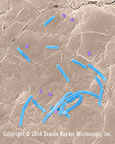

Bacillus anthracis Bacillus anthracis spore stage Bacillus anthracis spores. Bacillus anthracis Bacillus anthracis